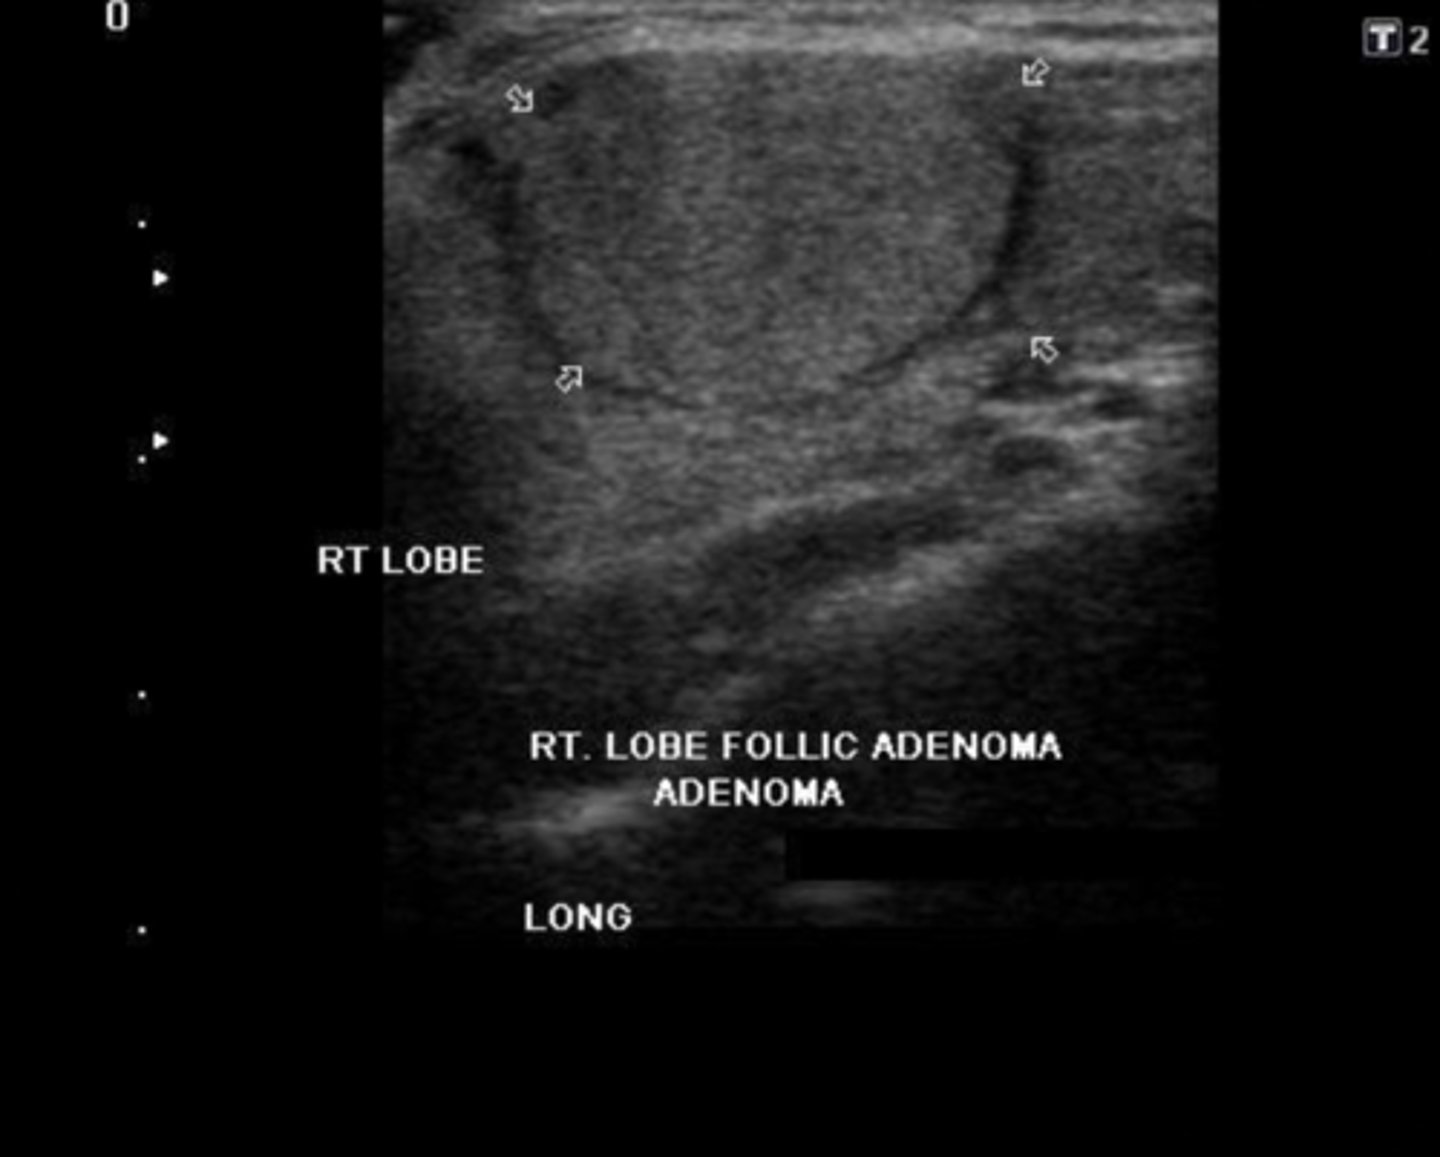

Benign Thyroid Neoplasms - Adenoma:

Sonographic findings

-Homogeneous _____ mass

-Prominent _____echoic peripheral halo

-_____ blood flow

-May degenerate and appear _____

-"_____" nodule on nuclear medicine scan

Etiology

-Composed of epithelial tissue

-Most common thyroid neoplasm

Clinical findings

-Asymptomatic

-Hyperthyroidism

-Female prevalence (7:1)

-Homogeneous echogenic mass

-Prominent hypoechoic peripheral halo

-Peripheral blood flow

-May degenerate and appear complex

-"Cold" nodule on nuclear medicine scan